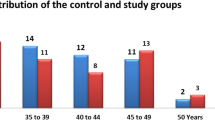

This study was approved by the Ethical Committee of Ningbo No.2 hospital. The 28 subjects involved in this study (7 males, 21 females; age 21.6 ± 7.9 years) presented with Class II malocclusion and were referred to the Orthodontic Center at Perfect Dental Care and the Department of Orthodontics, Zhejiang Chinese Medical University between January 2015 and December 2019. Inclusion criteria were as follows: (a) class II malocclusions with ANB larger than 3 degrees, (b) complete CBCT data were available at T0 and T1. Subjects were excluded if they presented skeletal asymmetries, unilateral posterior crossbite, articular noises at clinical examination (opening–closing), capsular or muscle pain, history of the orofacial trauma, articular systemic pathology, and history of orthodontic treatment. The average duration of treatment was 25 months.

However, due to the absence of a control group, we were unable to exclude the potential influence of age on condylar morphology. During adulthood, the condyle frequently undergoes remodeling processes that can impact its morphology [31]. Studies by Pontual et al. [32, 33] have shown an increased prevalence of degenerative bone changes with advancing age. Furthermore, it’s worth noting that 75% of the subjects in our study were female, which could introduce an additional factor affecting condylar remodeling. Epidemiological data indicates a strong female predilection for Temporomandibular Disorders (TMD), with an estimated male-to-female ratio of approximately 1:3 in TMD patients [34]. This predisposition is believed to be associated with female reproductive hormones, especially estrogen. Previous research has revealed that estrogen signaling pathways play a role in regulating pregnancy-related TMJ homeostasis [35]. A reduction in bone density can lead to TMJ degeneration. Another study found that Era polymorphism had an impact on altered mandibular dimensions in female symptomatic TMJ osteoarthritis patients, suggesting that estrogen may contribute to TMJ bone remodeling [36]. Additionally, the follow-up duration was not sufficient to capture long-term, longitudinal changes in subchondral bone in response to orthodontic treatment. Hence, future investigations should explore these long-term changes. Moreover, the study was limited by the relatively small number of patients due to its retrospective design. A well-designed prospective study can overcome this problem.